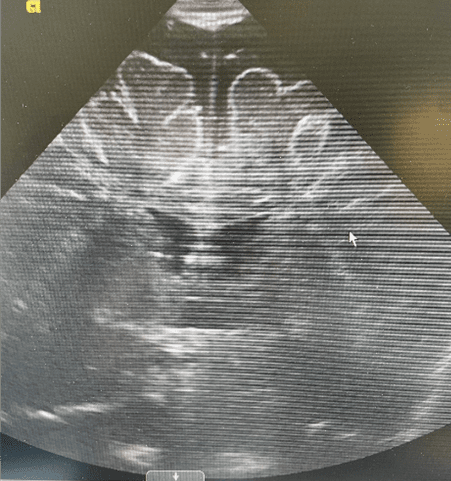

The first step in diagnosing hydrocephalus is often a through a clinical neurological evaluation. If the clinician suspects hydrocephalus, they will usually order imaging of the brain. The imaging may be an ultrasound, an MRI, or a CT scan. The physician may also decide to use a pressure monitoring technique such as placement of an ICP (intracranial pressure) monitor.